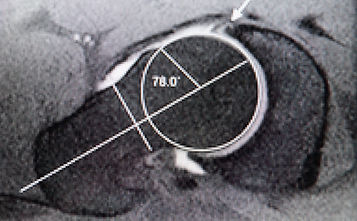

Альфа угол – угол между осью шейки бедра и линией, соединяющей центр головки бедра с местом перехода головки в шейку бедра (боковая проекция). Норма 42-47 град. «Сам» деформация – 65-70 град. (Альфа угол может также быть измерен при МРТ и КТ исследованиях.)